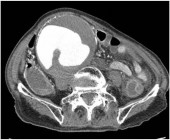

●県中2 60代F 急性腹症、Hb 4.0

【診断】 子宮巨大筋層内筋腫、子宮頚部の捻転、右卵巣からの出血性腹水